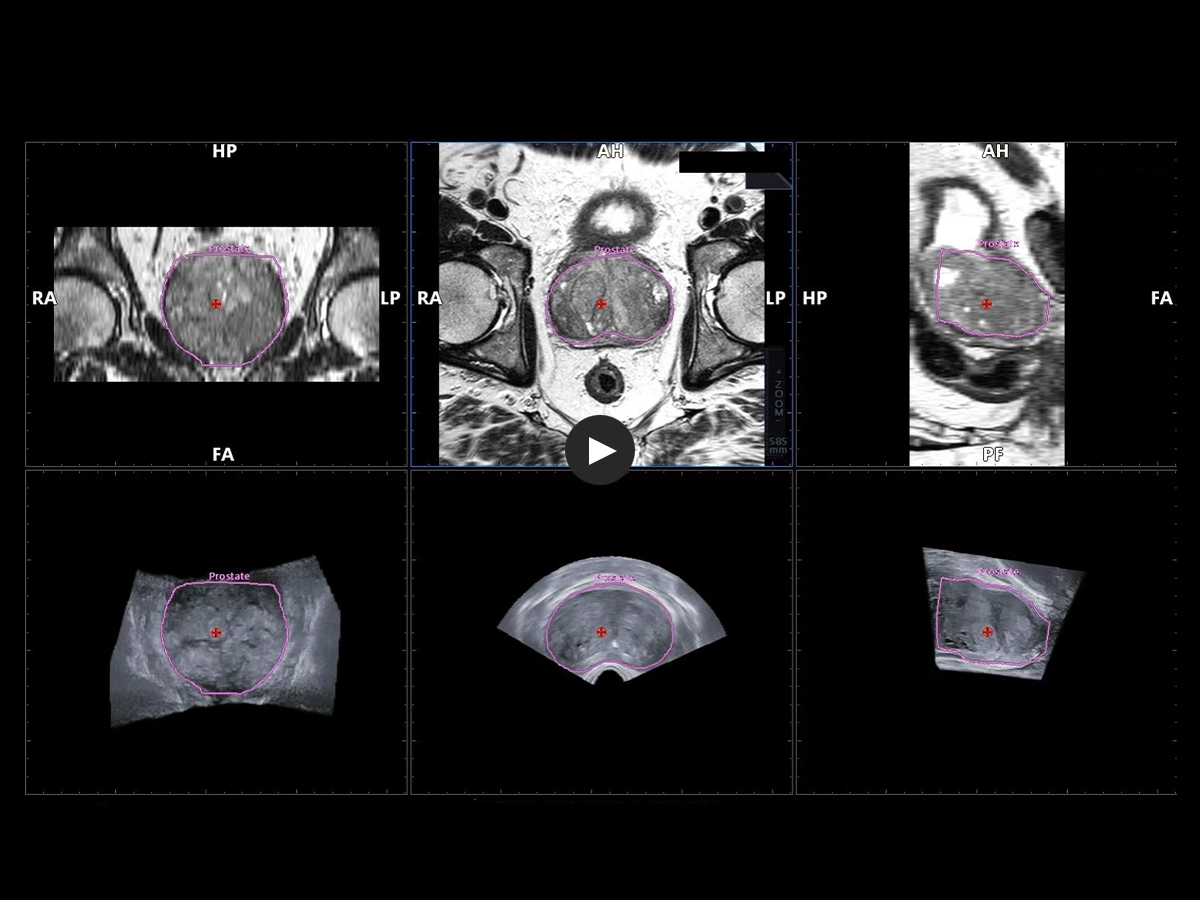

Expert users and beginners can now achieve a heightened degree of simplicity and precision by using UroFusion, Esaote’s cutting-edge fusion imaging solution that makes the most of the combination of US and MR or PET modalities.

By harnessing Augmented Insight™ (A.I.) technology, our dedicated solution enhances workflow efficiency by Automating MR Prostate Contouring & Segmentation with instant and automatic US-MR Synchronization, applied to both transperineal (TPUS) and transrectal (TRUS) prostate biopsy approaches.

Using UroFusion, clinicians will benefit from our intuitive tools to fasten the fusion procedures: the automatic prostate contouring and biopsy sample mapping are certainly the most impressive.

UroFusion seamlessly offers the ability to combine different mpMRI series, facilitating the identification of suspicious prostate lesions.

mpMRI targeting phase of PI-RADS 5 peripheral lesion